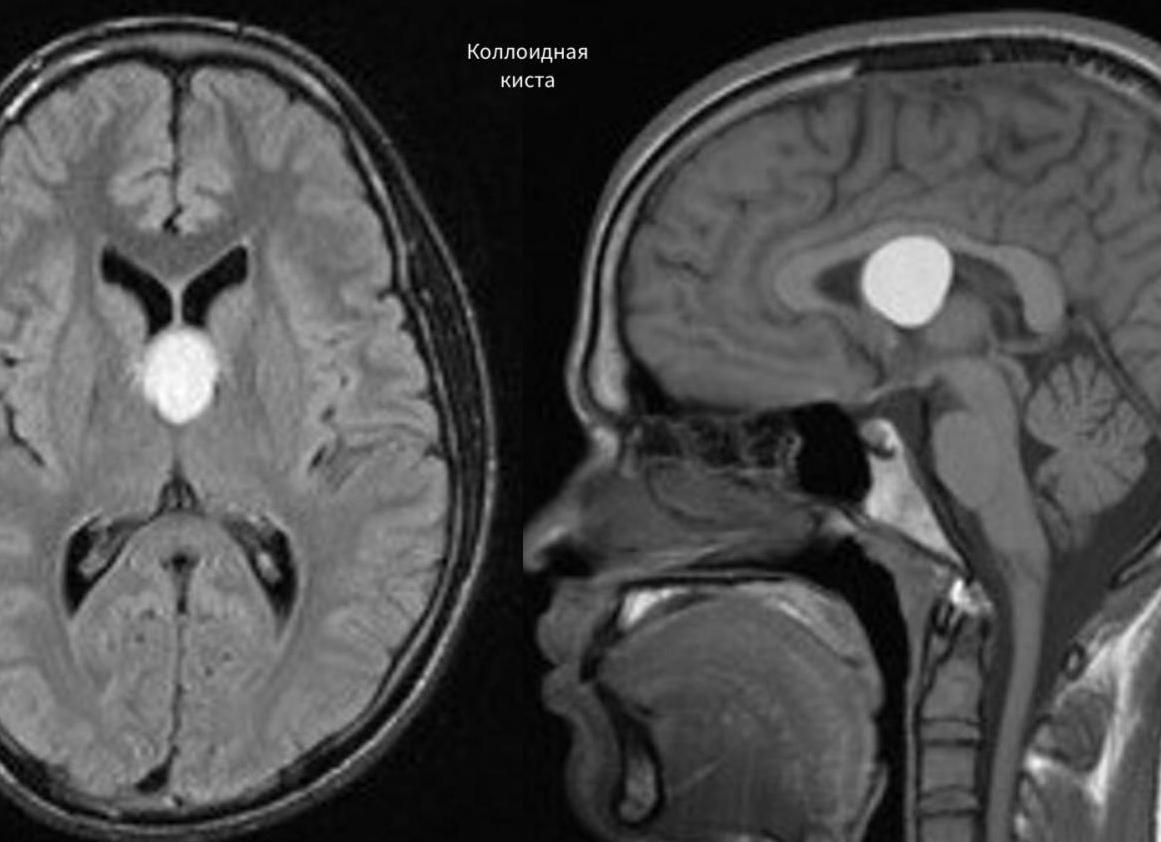

- Коллоидальная киста имеет врожденное происхождение. Она появляется в результате эмбиогенеза. Она может быть у человека всю жизнь, но при этом не доставляет ему никаких проблем. Есть мнение, что она носит наследственный характер. Эта киста блокирует поток жидкости. Она часто сопровождается головной болью, эпилептическими припадками, слабостью в ногах и высоким внутричерепным давлением. Наиболее ярко симптомы этого заболевания проявляются в зрелом возрасте. Иногда это заболевание является причиной возникновения гидроцефалии, мозговой грыжи. В редких случаях она приводит к летальному исходу.

Коллоидальная киста

- Коллоидальная киста. Врожденное образование малого размера, появляющееся в третьем желудочке мозга, чаще всего безопасно. Но если растет, то вызывает боли в голове, проявления эпилепсии, повышение внутричерепного давления, гипотонию (слабость) мышц ног, мозговые грыжи, водянку (гидроцефалию).

- Церебральная — внутримозговая развивающуюся внутри тканей головного мозга. На месте гибели клеток мозга появляется киста.Коллоидальная — образуется в 3 мозговом желудочке, не считается раковым заболеванием, но может прогрессировать и расти. Главная опасность наличия такой опухоли в голове заключается в том, что растущая киста может перекрыть доступ к путям ликвора и спровоцировать гидроцефальный синдром.